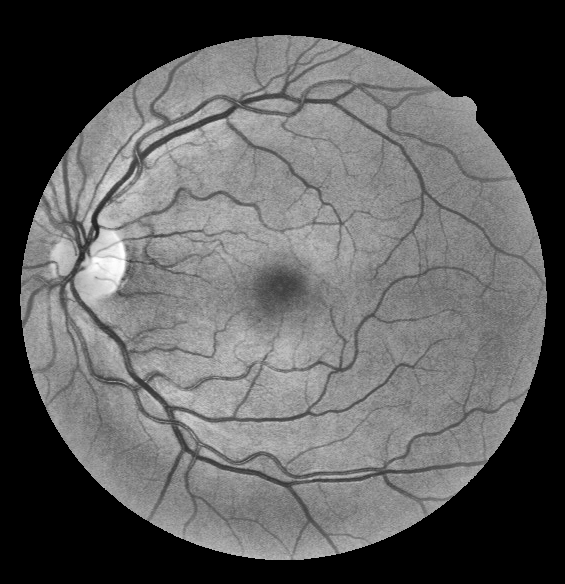

Retinal vessel segmentation is an essential step for fundus image analysis. With the recent advances of deep learning technologies, many convolutional neural networks have been applied in this field, including the successful U-Net. In this work, we firstly modify the U-Net with functional blocks aiming to pursue higher performance. The absence of the expected performance boost then lead us to dig into the opposite direction of shrinking the U-Net and exploring the extreme conditions such that its segmentation performance is maintained. Experiment series to simplify the network structure, reduce the network size and restrict the training conditions are designed. Results show that for retinal vessel segmentation on DRIVE database, U-Net does not degenerate until surprisingly acute conditions: one level, one filter in convolutional layers, and one training sample. This experimental discovery is both counter-intuitive and worthwhile. Not only are the extremes of the U-Net explored on a well-studied application, but also one intriguing warning is raised for the research methodology which seeks for marginal performance enhancement regardless of the resource cost.

Segmentation of retinal vessels is a crucial step in fundus image analysis. It provides information of the distribution, thickness and curvature of the retinal vessels, thus greatly assists early stage diagnosis of circulate system related diseases, such as diabetic retinopathy. Researchers have devoted to this field for decades [1], and with the development of deep learning technologies [2], many deep networks have been proposed to tackle this problem. For instance, a Convolutional Neural Network (CNN) combined with conditional random field in [3], a network pipeline concatenating a preprocessing net and a vesselness Frangi-Net in [4], and the U-Net [5]. Since published, U-Net has achieved remarkable performance in various fields. Researchers [6] even claim that hyper-parameter tuning the U-Net rather than constructing new CNN architectures is the key to high performance. However, U-Net generally contains huge amounts of parameters and is resource consuming. Previously, researchers [7] have proposed to prune U-Net levels in the testing phase to reduce the network size. Yet the modifications introduce even more parameters in the training phase, and only one decisive factor of the architecture, the number of levels, is considered.

We work on retinal vessel segmentation on the DRIVE database and start with a three-level U-Net with 16 filters in the input layer. Firstly, we aim to enhance its performance by integrating common deep learning blocks into the architecture. As the expected performance boost is not observed, we propose the assumption that the basic U-Net alone is adequate or even overqualified for the task. To verify this hypothesis, we design an experiment series to compress the basic U-Net. The number of levels, convolutional layers per level, and filters per convolutional layer are reduced respectively. Non-linear activation layers are removed, and the number of training sets are decreased to further delve into the limits of the network training procedure. Results show that surprisingly harsh conditions are required for the U-Net to degenerate, indicating that the default configuration is redundant. Our contributions are two-fold: the minimum U-Net for this task is reported, indicating the possibility of real-time retinal vessel segmentation on mobile devices; and the issue of excessive computational power use is exposed and stressed on.

2.4 Database Description

All experiments are trained and evaluated on the Digital Retinal Images for Vessel Extraction (DRIVE) database. DRIVE is composed of 40 RGB fundus photographs with the size of pixels. All images are provided with manual labels and Field of View (FOV) masks. The database is equally divided into one training and testing set. A subset containing four images is randomly selected from the training set for validation.

The raw images are prepared with a preprocessing pipeline, where the green channels are extracted, the inhomogeneous illumination is balanced with CLAHE, and pixel intensities within the FOV masks are standardized to (-1, 1). The borders of all FOV masks are eroded by four pixels to remove potential border effects and ensure meaningful comparison. Additionally, multiplicative pixel-wise weight maps are generated from the manual labels to emphasize on thin vessels using the equation: , where represents the vessel diameter in the given manual label, and is manually set to .